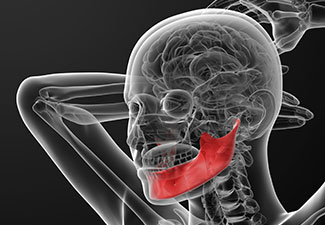

Τα διφωσφονικά σχετίζονται με την οστεονέκρωση της γνάθου.

Η ισχυρή αναστολή της λειτουργίας των οστεοκλαστών σε θεραπεία με διφωσφονικά μπορεί να οδηγήσει σε αναστολή της φυσιολογικής ανανέωσης των οστών, οδηγώντας σε διαταραχή της επούλωσης του τραύματος μετά από τραυματισμό (όπως, σε οδοντιατρική χειρουργική επέμβαση) ή ακόμη και  μη επούλωση των οστών.

Όταν χορηγούνται διφωσφονικά ο κίνδυνος για οστεονέκρωση γνάθου είναι αυξημένος.